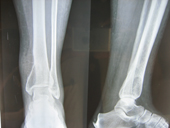

| Giant cell tumour tibia pre op |

Giant cell tumour tibia post op |

Joseph Hospital's Tumor & Bone disease service benefits from the experience and expertise of experts.The team treats bone tumors and soft tissue tumors in collobaration with Radiotherapists and Surgical Oncologists . Limb salvage is done with radical excision of the tumour and reconstruction with prosthesis in lieu of amputations.